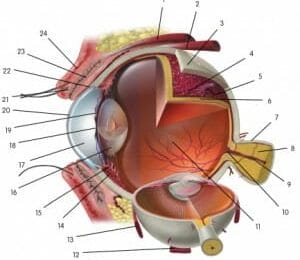

Obliquus inferior

De bewegingen van de oogbollen worden gecontroleerd doo...

Lees Meer +

Levator palpebrae superioris

De musculus levator palpebrae superioris is een dunne, ...

Lees Meer +